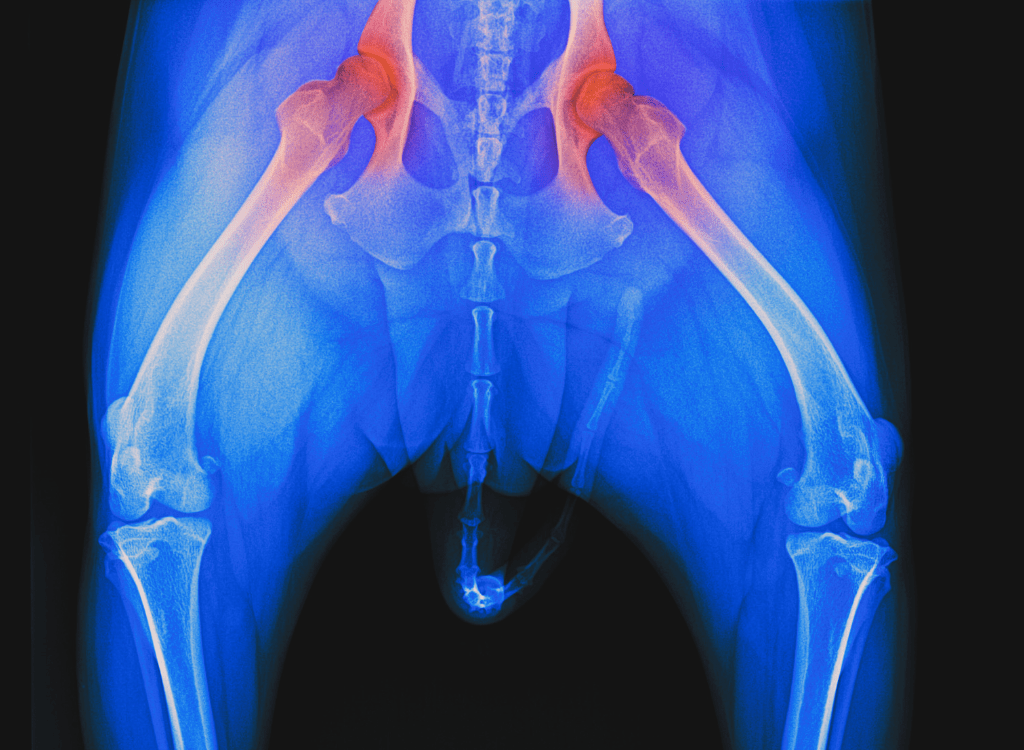

A dog’s joints act as flexible connectors that support running, jumping, turning, and every playful wiggle. When these joints weaken, mobility declines. Common issues include arthritis, hip dysplasia, ligament injuries, and age-related degeneration. Genetics, body weight, and exercise style all influence how quickly joint problems appear. Understanding how these joints work allows you to choose exercises that protect rather than stress them.